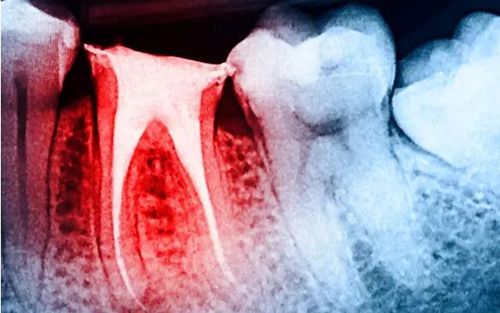

大量研究表明:與活髓牙相比,根管治療后牙體組織的強(qiáng)度、韌性以及硬度等力學(xué)性能均無明顯改變,牙髓活力對(duì)牙齒的生物力學(xué)性能的影響十分有限;而齲損組織、舊充填物和后續(xù)的治療修復(fù)過程造成的冠根部牙體組織的喪失才是引起牙齒抗折強(qiáng)度降低的主要原因。牙體強(qiáng)度與剩余牙體組織的量密切相關(guān),牙體組織缺損愈多,抗折力降低愈明顯。